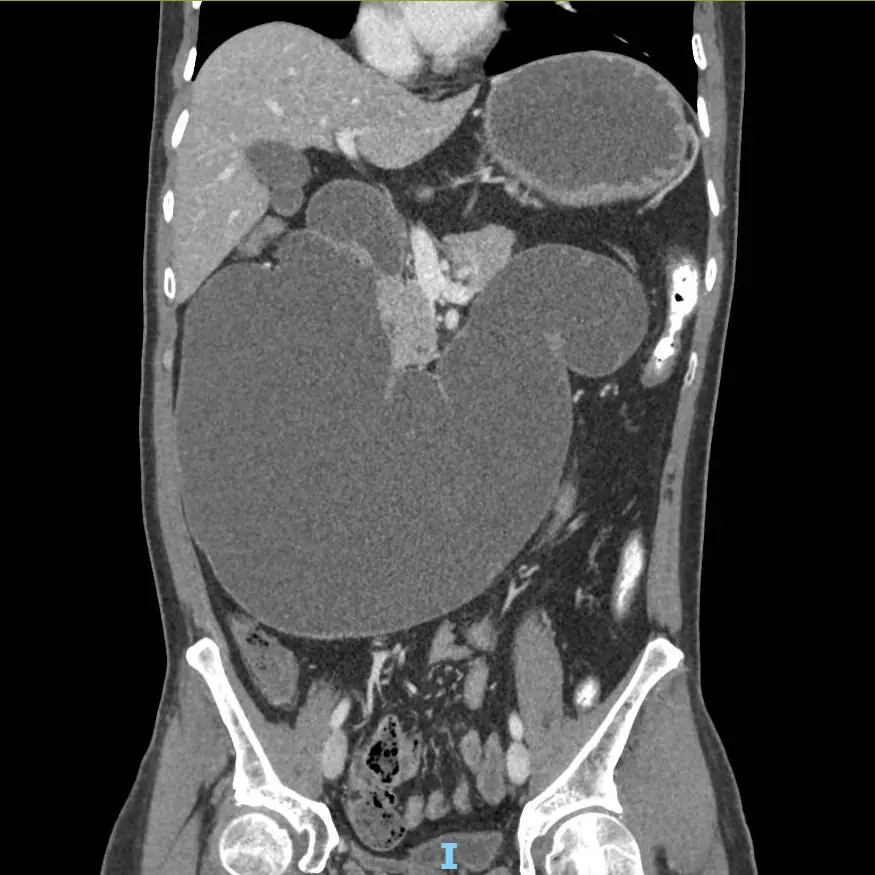

Anh Y.C.S. (42 tuổi, Campuchia) nhập viện FV trong tình trạng nguy kịch: nôn ra máu, sốc do thiếu máu và thiếu dịch, cơ thể suy kiệt, bụng chướng to bất thường. Kết quả CT scan khiến các bác sĩ kinh ngạc: dạ dày, tá tràng đã giãn cực đại, chiếm gần toàn bộ khoang bụng.

“Tá tràng là đoạn đầu tiên của ruột non, nối với dạ dày, dài khoảng 25cm. Ở người bình thường, tá tràng trong trạng thái xẹp, kích thước to chừng ngón tay, khi thức ăn đi vào thì giãn ra bằng đầu ngón chân cái. Riêng bệnh nhân này, khẩu kính tá tràng đo được có đường kính 12cm, chu vi 38cm, to bằng ống tay áo”, bác sĩ Thái cho hay.

Một dấu hiệu khá lạ và có ý nghĩa ghi nhận trong quá trình theo dõi ở ca bệnh này, đó là dạ dày đã xẹp và co lại rõ rệt sau khi đặt ống thông mũi – dạ dày – tá tràng 3 ngày, nhưng tá tràng thì không. Tá tràng vẫn giãn cực đại, dính vào các cơ quan xung quanh, gần như chiếm trọn không gian nội tạng phần bụng chậu và mất hoàn toàn chức năng co bóp.

Hình ảnh chụp cắt lớp vi tính: tá tràng giãn khổng lồ chiếm gần hết khoang bụng

Hình ảnh chụp cắt lớp vi tính: tá tràng giãn khổng lồ